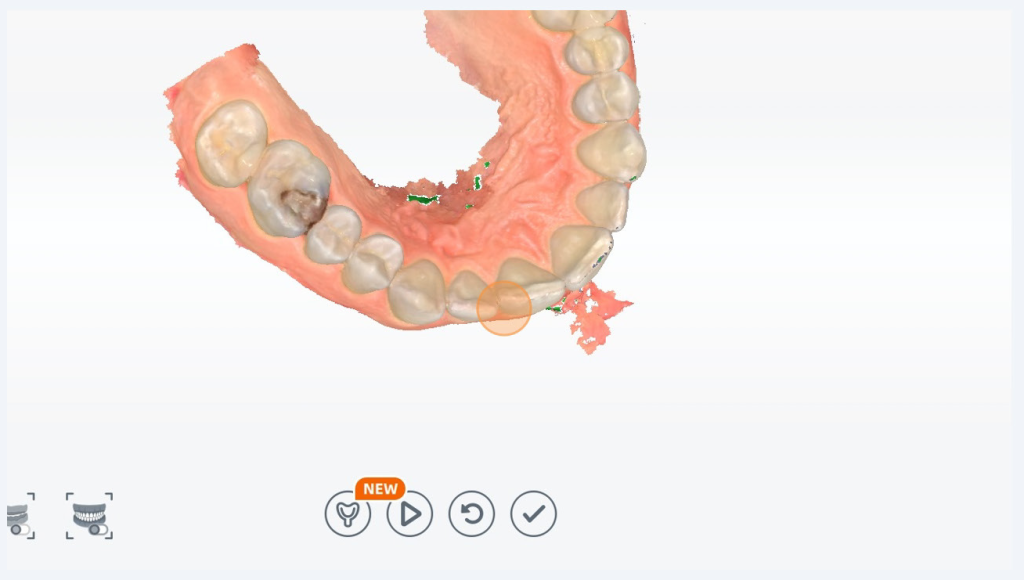

Any areas marked in green can be filled in with scan data by unpausing your scanner and scanning over the area again.

Now we have moved onto preparing for the post prep scan. We need to make a hole in the scan where the pre prep scan has a tooth.

Move the scan around by using the left mouse button to TILT and the center mouse wheel button to PAN, and roll your mouse wheel to ZOOM

Move the scan until the blue circle is larger than the entire tooth you have prepped. Then double click

Now you have a hole in the scan. Click Finish.